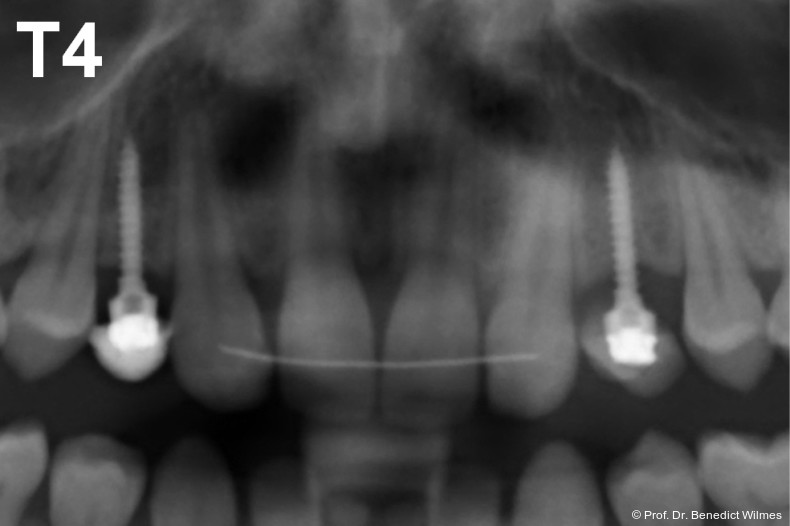

Ein 14-jähriger Patient wurde bei Aplasie der beiden oberen seitlichen Schneidezähne mit dem Ziel der beidseitigen Lückenöffnung kieferorthopädisch therapiert (Abb. 1a+b). Zum Ende der kieferorthopädischen Behandlung wurden zwei Miniimplantate in Regio 2er als temporärer Zahnersatz inseriert (Benefit System, PSM, 2 x 13 mm, Abb. 2a+b). Nach Abdrucknahme wurden Kronen auf den Peek-Abutments modelliert und diese mit Kunststoff auf die Abutments geklebt (Abb. 3a–d). In den Abbildungen 3 und 4 sind die klinischen und röntgenologischen Nachkontrollen innerhalb der nächsten achteinhalb Jahre dokumentiert. Man erkennt einen sowohl in der Höhe als auch in bukkopalatinalen Breite verbleibenden gesunden Knochen ohne Anzeichen einer Atrophie. Im Alter von 23 Jahren wurden die definitiven Implantate ohne die Notwendigkeit einer Augmentation eingesetzt (Abb. 5) und nach Einheilung prothetisch versorgt (Abb. 6a–e und Abb. 7a–c).

Nach Abschluss der kieferorthopädischen Pfeilerverteilung wurden zwei Miniimplantate in Regio 3er inseriert (2 x 13 mm). Nach Herstellung im Labor wurden Kronen auf den Miniimplantaten aufgeschraubt (Abb. 13+16a–d). Auch hier wurde darauf geachtet, dass die Kronen aus der Okklusion geschliffen wurden (Abb. 14). Bei den Nachkontrollen zeigten sich ebenfalls stabile Miniimplantate und ein entzündungsfreies Implantatlager ohne erkennbare Atrophie des Knochens (Abb. 15 und 16a–d).

Eine lokale Hemmung des alveolären Wachstums wurde klinisch nur in einem geringen Ausmaß beobachtet, was wahrscheinlich an dem verglichen mit den dentalen Implantaten geringeren Durchmesser liegt. Weitere Studien mit dreidimensionaler Evaluation der knöchernen Situation über den Zeitraum der Nutzung sind nun ratsam, um die Entwicklung des ortständigen Knochens auch quantitativ zu evaluieren.